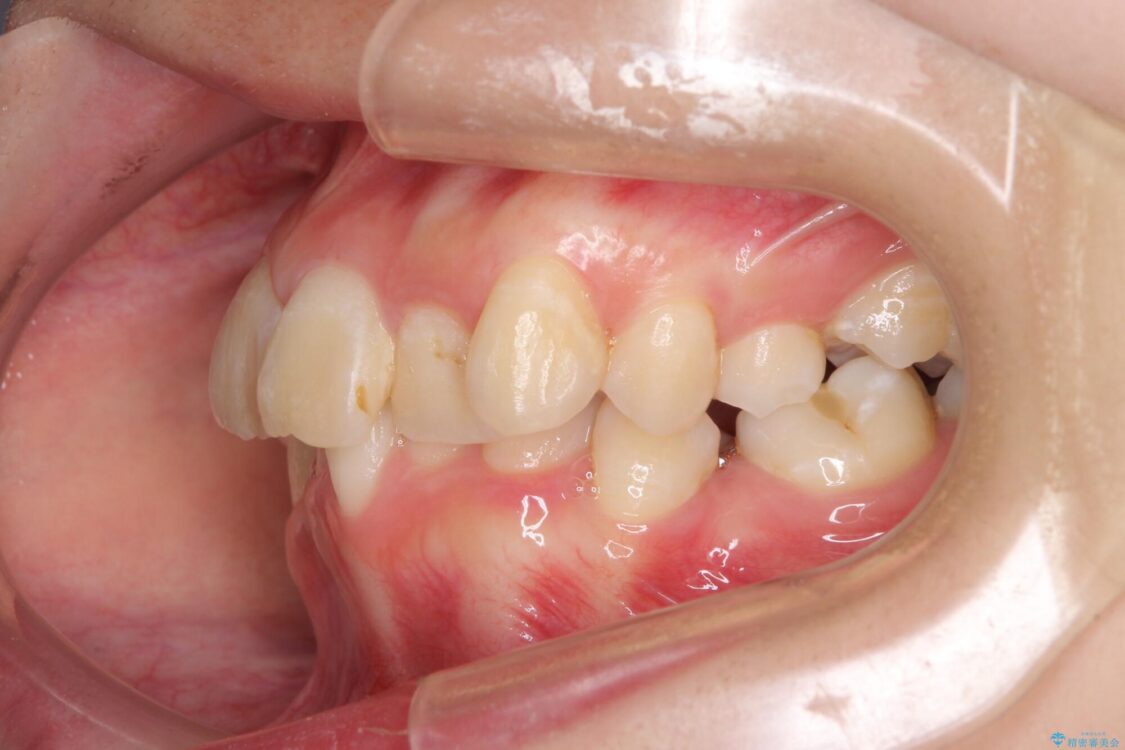

治療途中

• デコボコと深い咬み合わせ ワイヤー装置での抜歯矯正 治療途中画像